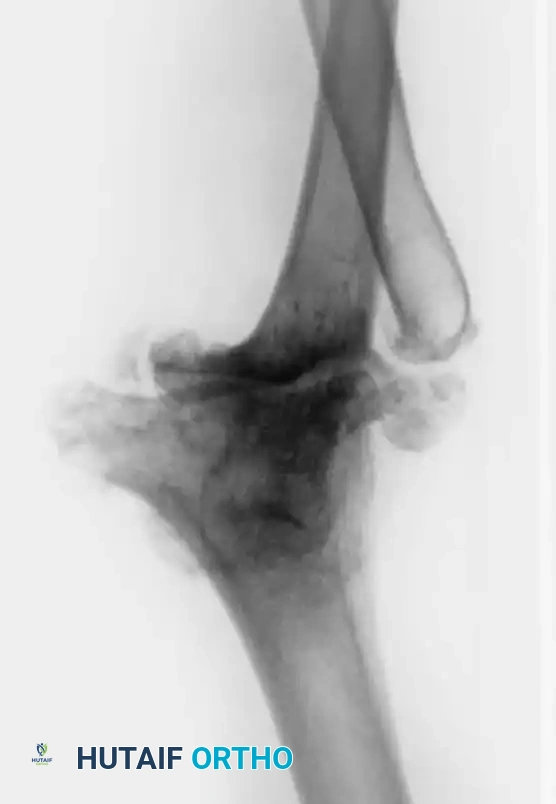

Associated Surgical & Radiographic Imaging